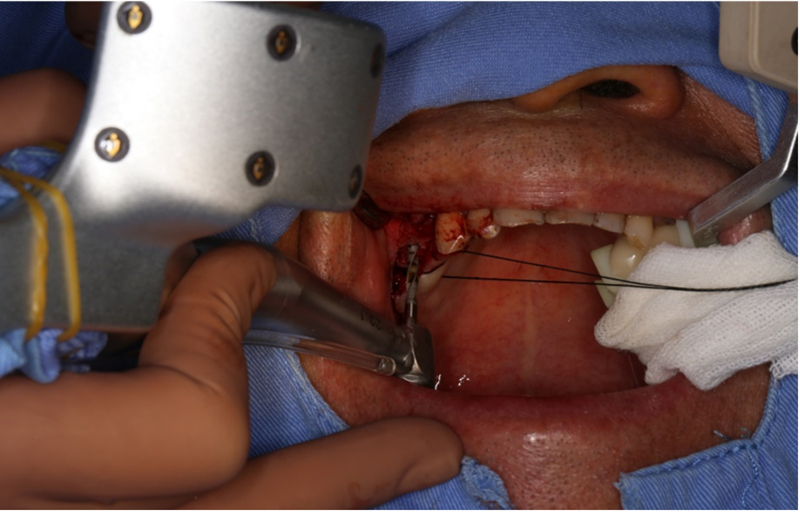

®完成標定及配準

®按照術前方案進行備洞及植體植入

®按照術前方案進行備洞及植體植入,醫(yī)生可以通過屏幕軟件引導對手術中植入點、角度、深度實時追蹤